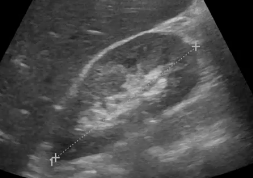

Pelvis : Caractérisation des masses annexielles de l'abdomen aigu à l'incidentalome

HOTTAT N. - ULB

Année académique 2021-2022

Imagerie de la femme DES SPECIALITE